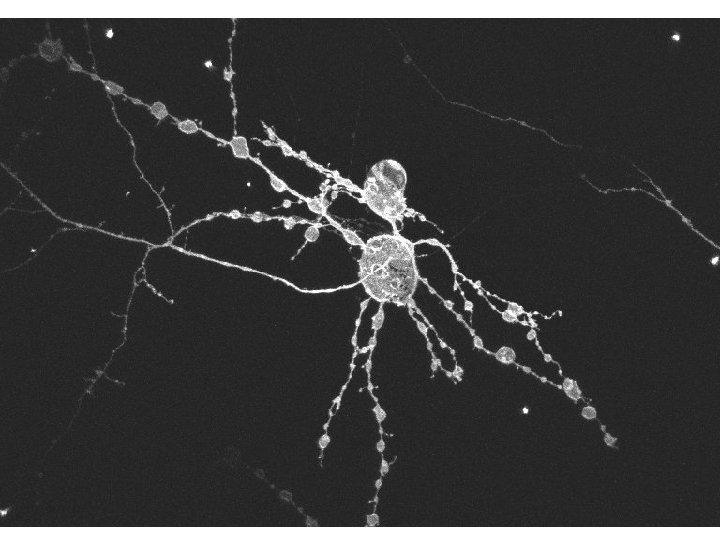

Anatomy of the axon

Axons behave very differently from dendrites In Health (their physiological role) And in Disease (their pathological response)

Axon Anatomy Axons are cables composed of a tube surrounded by a cell membrane +/insulation (myelin). From: Li S, Mealing GA, Morley P, Stys PK J Neurosci 1999 Jul 15; 19(14): RC 16